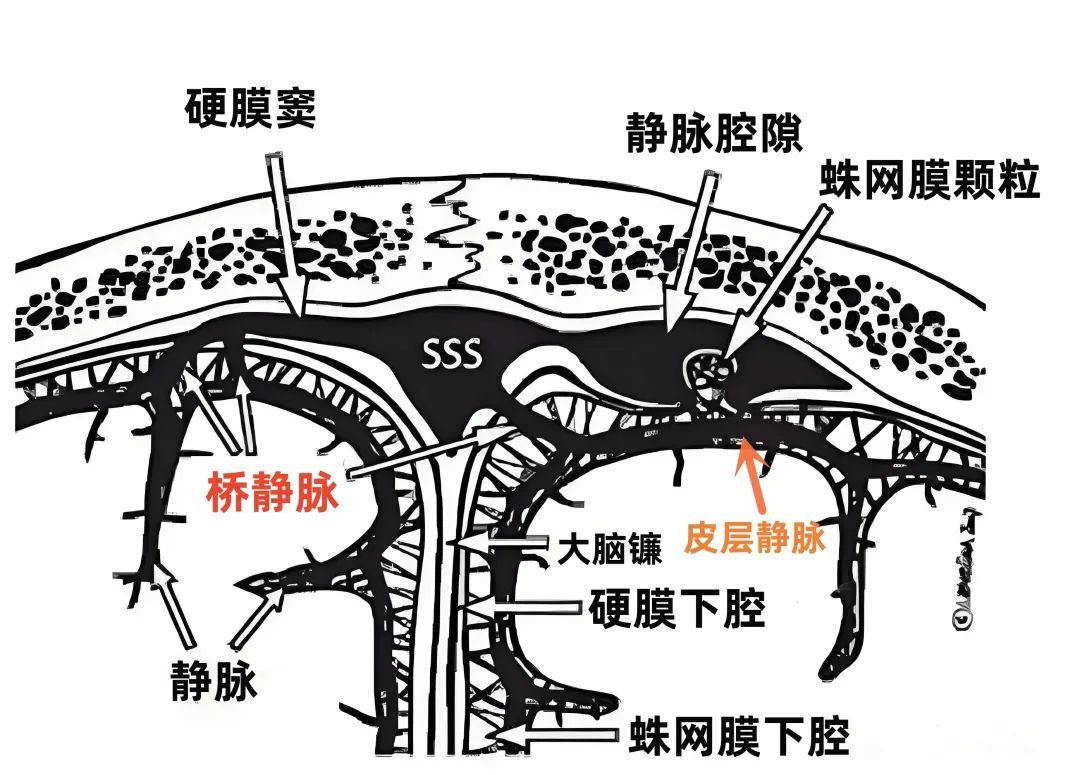

上矢状窦(superior sagittal sinus SSS)位于中线,引流额叶下面的前部和额叶、顶叶、枕叶外侧面及内侧面的上部。 上矢状窦的冠状切面呈三角形,左右两个侧角与覆盖半球凸面的硬脑膜相连接,下角与大脑镰相连。上矢状窦的三角形管腔前部较细,向后逐渐扩大。 上矢状窦两侧壁有的地方向外膨隆扩张,形成外侧陷窝。外侧陷窝常有大脑皮层静脉汇入,还有蛛网膜颗粒突入其中。上矢状窦的下角和外侧陷窝之间常有许多横行的纤维相连。在上矢状窦后部的窦壁内有一海绵状间隙系统,在窦壁内皮与硬脑膜之间,形成海绵状间隙,参与调节脑血流量。

静脉腔隙(Venous lacunae),也称为静脉湖、静脉间腔、静脉间隙,来自硬脑膜的引流静脉在上矢状窦附近扩大形成静脉腔隙,它位于两层硬脑膜之间(下图)。 静脉腔隙主要接受硬脑膜内硬脑膜静脉的回流,也引流板障静脉的血液。 静脉腔隙内壁有蛛网膜颗粒(上图),进入上矢状窦的皮层静脉(上图)往往在静脉腔隙下方走行,直接汇入矢状窦,而不是直接进入静脉腔隙。大部分途经静脉腔隙下方的静脉与静脉腔隙分别开口入窦,但有些静脉与静脉腔隙有共同的入窦开口,极少数的静脉直接引流入静脉腔隙。 也有桥静脉(上图)先在窦旁潜行进入硬膜再汇入窦,硬膜内潜行使空腔扩大形成硬膜窦。静脉腔隙和硬膜窦都与矢状窦相通。 额叶后部和顶部的静脉腔隙最大和最恒定,枕部和额叶前部的静脉腔隙较小(上图)。 通常每侧都有2或3个这样的静脉腔隙,额部一个小静脉腔隙,顶部一个大的静脉腔隙,枕部一个大小介于前两者之间的静脉腔隙。 在年龄大的个体,这些腔隙趋向于融合,以致于每侧形成一个纵长的腔隙(下图)。 下图示切除大的静脉腔隙,显露下方进入上矢状窦的静脉。左侧中央静脉在中央沟上端注入上矢状窦。右侧中央静脉向前越过中央前回加入上矢状窦。

多数皮层静脉由单根起始,逐渐接受属支。相邻区域的皮层静脉可汇合成为一支桥静脉,穿出蛛网膜下腔,最后汇入硬膜窦。另外,引流半球内侧、外侧和底面的静脉,可能在交界区形成为一支桥静脉,最后汇入一个静脉窦。大脑内侧和外侧的上升静脉经常在半球上缘汇合,并进入上矢状窦;半球外侧下降的引流静脉和半球底面向外的引流静脉可在半球下缘汇合,进入颅底的硬膜窦。少数皮层静脉加入脑深部静脉系统。 相邻区域的血管间有互补关系,即某一静脉引流的区域增多,则相邻静脉的引流范围随之减少。在脑叶或面的主要引流静脉组之间也有类似的互补关系。

上矢状窦组(上图 深蓝色)由回流至上矢状窦的静脉组成,包括引流额叶、顶叶、枕叶内侧、外侧面上部皮层以及额叶眶面前部的静脉。 注入上矢状窦的大脑外侧面静脉包括额极静脉、额前静脉,额中静脉、额后静脉,中央前静脉、中央静脉、顶前静脉、顶后静脉、枕静脉和Trolard静脉。 注入上矢状窦的大脑内侧面静脉(上图 蓝色)包括额前内侧静脉,额中内侧静脉、额后内侧静脉、旁中央沟静脉、顶前内侧静脉、顶后内侧静脉和距状后静脉。 一般静脉在离开软膜-蛛网膜注入上矢状窦前,会在硬膜下腔有1~2cm长的游离段。这些静脉可能直接汇入上矢状窦,也可能先汇入硬膜内的硬膜窦,再进入上矢状窦。